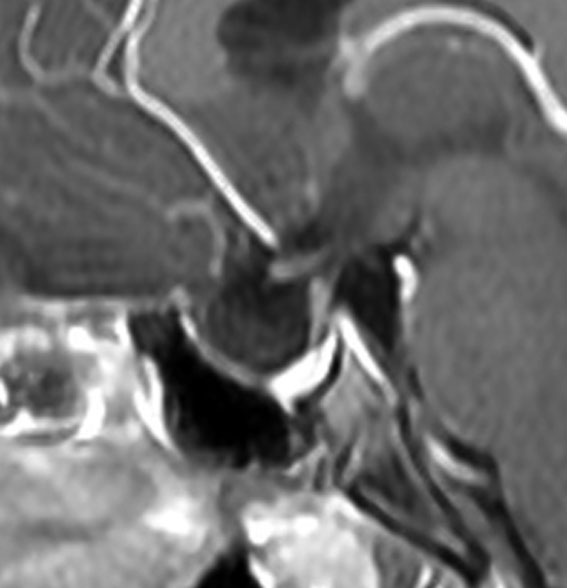

この患者さんは軽い下垂体機能低下症で発症しました。蝶形骨洞の中にのう胞が拡大していて,下垂体がぺったんこです。鞍上部には全く伸びていないので,視神経交叉は正常に見えます。この手術はとても簡単です,嚢胞をぷつんと破って液体を排出するだけにした方がいいでしょう。何故なら下垂体がうすく菲薄化funningしているので嚢胞壁を摘出しようとすると前葉機能を低下させるリスクが高いからです。